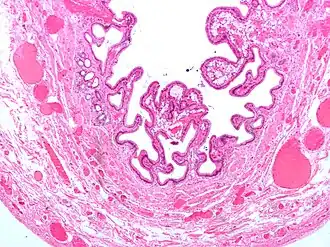

Micrografia da vesícula biliar com colecistite e colesterolose.

Colecistite crónica

A colecistite crónica resulta da inflamação continua de baixo grau da vesícula, ou de vários ataques autolimitados de colecistite aguda. Microscopicamente o infiltrado inflamatório é constituido por macrófagos, que ingerem as membranas celulares das células destruídas, apresentando-se cheios de lípidos: macrófagos xantelesmizados. Além disso são visíveis seios de Rokitansky-Aschoff: ou evaginações na membrana devido a menor taxa de renovação da mucosa que de destruição. Por vezes à calcificação da mucosa, denominada de vesícula de porcelana: nestes casos o risco de cancro da vesícula é muito mais alto.